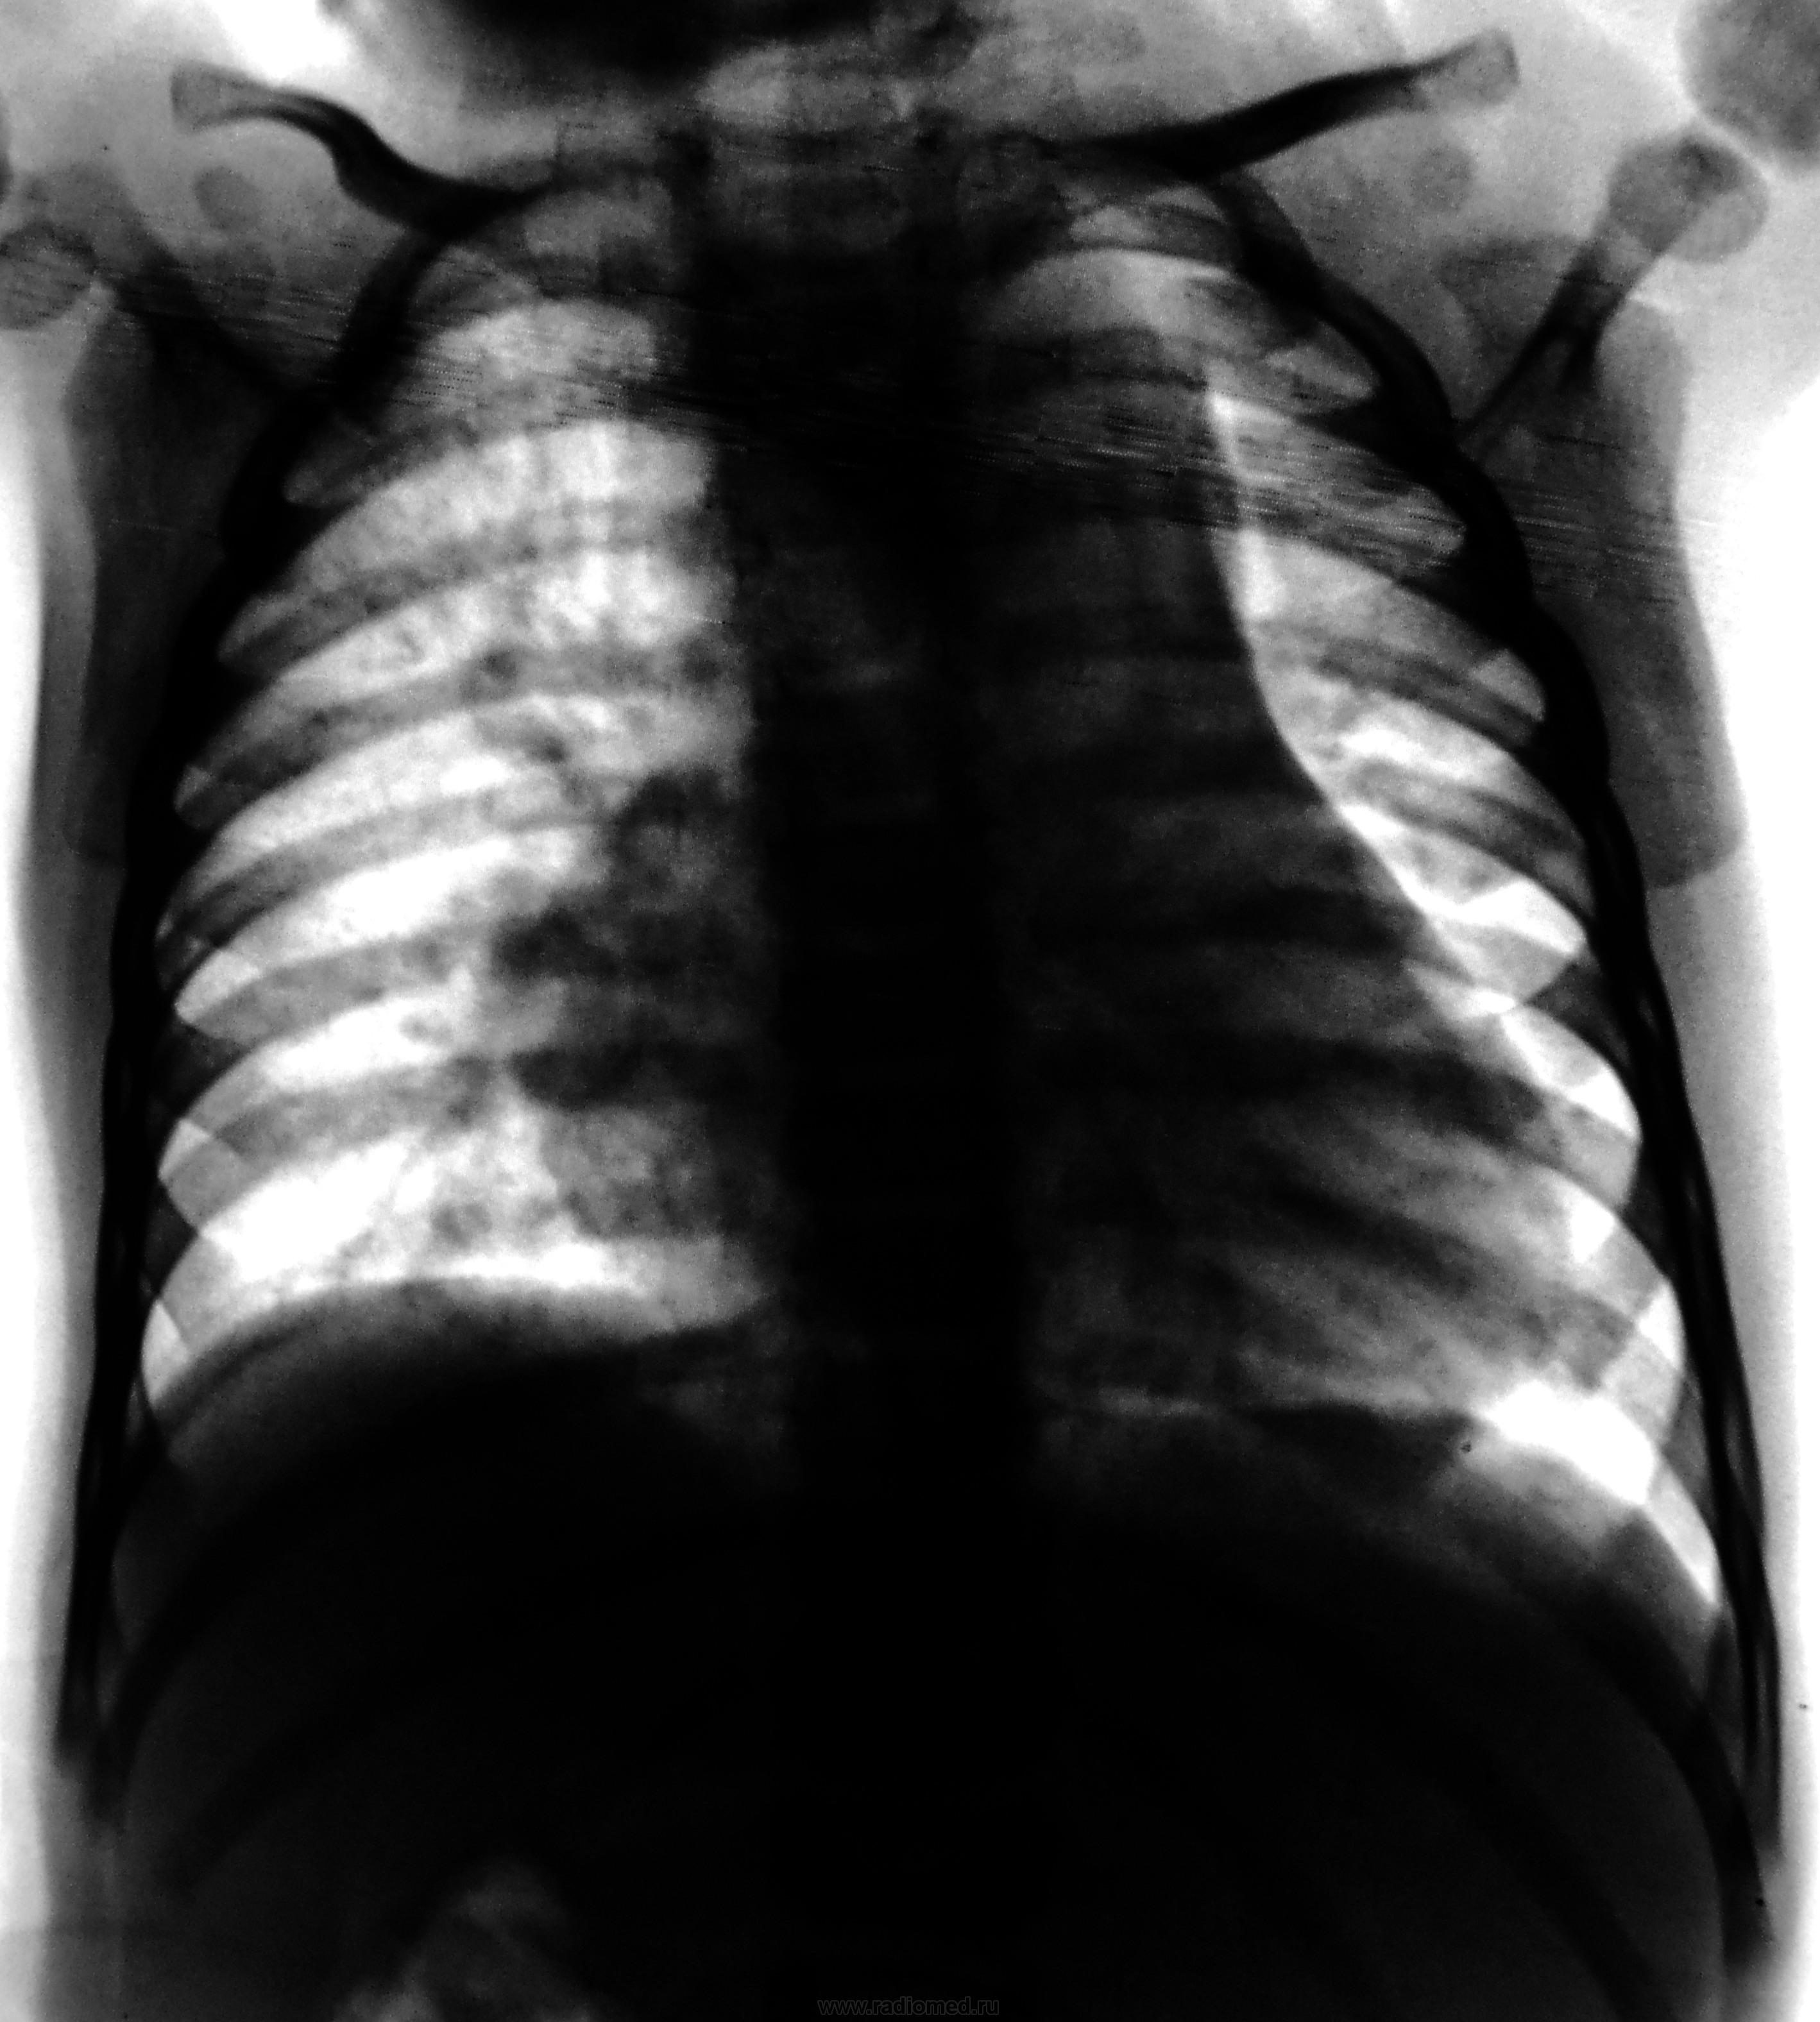

Пол пациента: Женский пол Тип патологии: Другое Область исследования: Грудная клетка и верхние дыхательные пути Методы исследования: Rg Пациент направлен на рентгенографию ОГК с диагнозом - "врожденный порок" https://radiomed.ru/sites/default/files/styles/case_slider_image/public/user/12/2.dscn0454a.jpg?itok=NsBvrkBp https://radiomed.ru/sites/default/files/styles/case_slider_image/public/user/12/3.dscn0455.jpg?itok=JbtadSKP ID:24004 Пнд, 29/10/2012 - 19:49 #1 И.Бондаренко Не на сайте Был на сайте: 1 день 22 часа назад Зарегистрирован: 13.09.2011 - 22:55 Публикации: 9206 Какой возраст "врожденного порока"? Пнд, 29/10/2012 - 20:10 #2 Катенёв Валенти... Не на сайте Был на сайте: 7 лет 2 недели назад Зарегистрирован: 22.03.2008 - 22:15 Публикации: 54876 1 год и 4 месяца. Пнд, 29/10/2012 - 21:23 #3 Dr.Yllich Не на сайте Был на сайте: 1 год 4 месяцев назад Зарегистрирован: 01.05.2011 - 22:52 Публикации: 1196 Размеры и форма сердечной тени "годятся" для врожденного порока, но ЭХО-кардиография обладает гораздо большими возможностями в этих вопросах, чем обзорная рентгенография. С уважением. Ильич. Втр, 30/10/2012 - 17:02 #4 Santuus Не на сайте Был на сайте: 2 года 5 месяцев назад Зарегистрирован: 01.07.2009 - 23:08 Публикации: 109 Согласен с доктором Dr.Yllich

1 год и 4 месяца.

Размеры и форма сердечной тени "годятся" для врожденного порока, но ЭХО-кардиография обладает гораздо большими возможностями в этих вопросах, чем обзорная рентгенография.